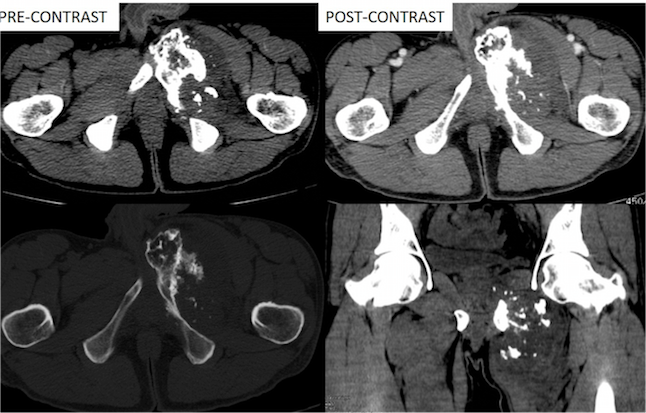

Figure 3. A large intramedullary mass lesion is noted arising from the body and near a portion of the left superior and inferior pubic rami. The lesion appears hyperintense on T2WI, STIR and hypointense on T1WI. The lesion has a short bony stalk with direct continuation with the underlying bone.

Figure 4. The lesion shows heterogeneous contrast enhancement.

MRI with and without contrast

A large intramedullary mass lesion of 9.5x8x11 cm was noted arising from the body and near portion of left superior and inferior pubic rami. The lesion appears hyperintense on T2WI, STIR and hypointense on T1WI. The lesion has a short bony stalk with direct continuation with the underlying bone.

The bulk of the tumor is noted to protrude into the medial aspect of the left upper thigh, elevating the gracilis and adductor muscle with altered signal intensity (hyperintense on T2WI, STIR) within it. On post-contrast study, the lesion shows heterogeneous enhancement.

Above findings of large cartilaginous matrix tumor with heterogeneous contrast enhancement, cortical expansion, and destruction suggests chondrosarcoma.